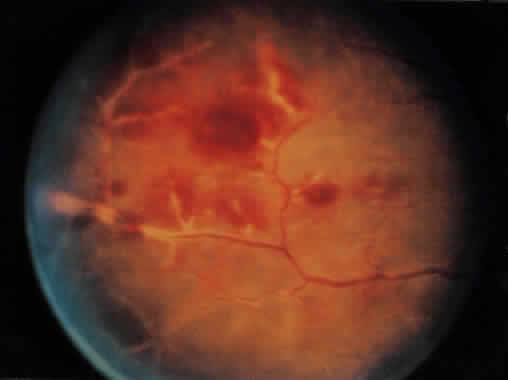

A Japanese national survey of BD has shown that ocular symptoms occur in 86% of patients with BD.40 Common clinical presentations include anterior uveitis with hypopyon (Fig. 4), vitritis, retinal vasculitis (Figs. 5 and 6), and chronic ischemic optic neuropathy. The hypopyon in BD has been shown to be composed of neutrophils41 and, in its later stages, lymphocytes as well.42 The disease tends to have a remitting-relapsing clinical course and carries a high potential for visually devastating complications.

Fig. 6. Occlusive retinal vasculitis in a patient with Behçet's disease.